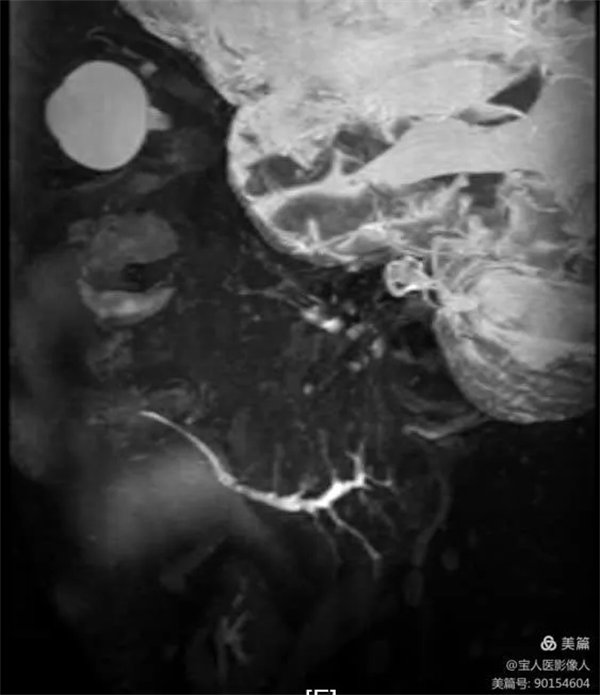

患者磁共振檢查,可清晰地顯示正常腮腺導管主干和大分支導管。

圖1,右側腮腺主導管和分支